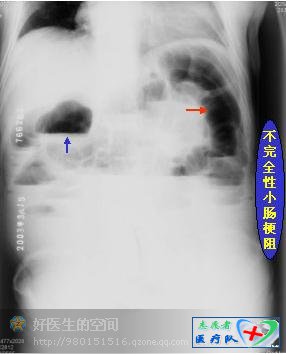

麻痹性肠梗阻:表现为全腹内肠管轻中度扩张,积气多、积液小,即液平面短小。